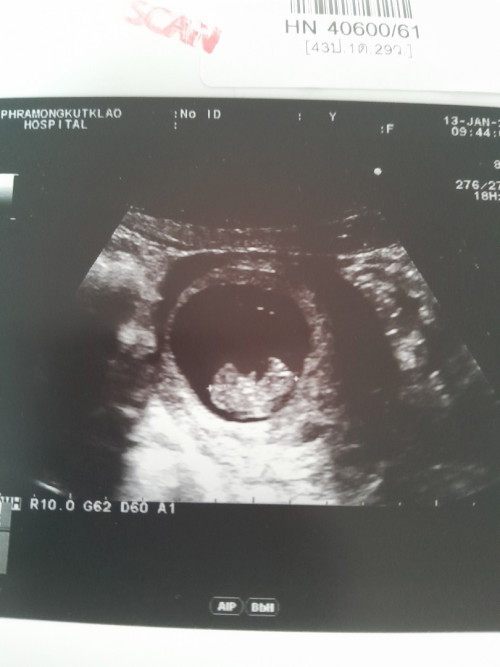

ไปซาวมาเมื่อวาน 10w4d

9.2สัปดาห์ค่ะ